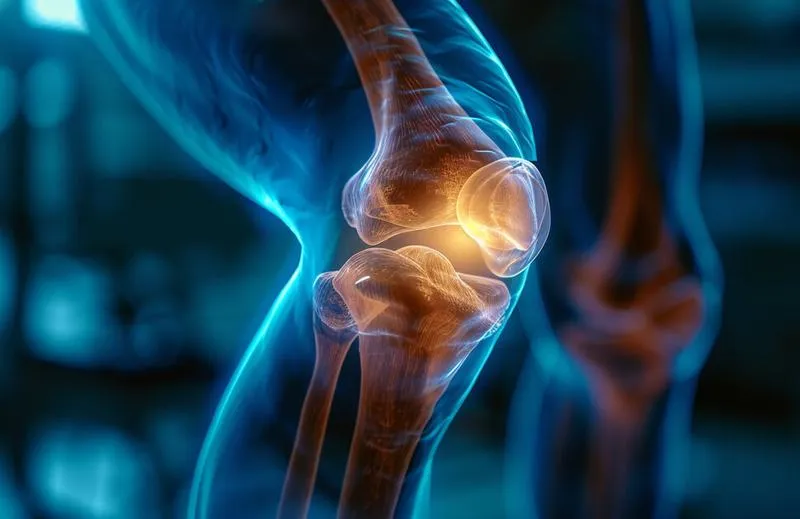

Rehabilitacja po urazie łąkotki to temat, który wzbudza wiele emocji. Każda osoba doświadczająca bólu stawu kolanowego z pewn...